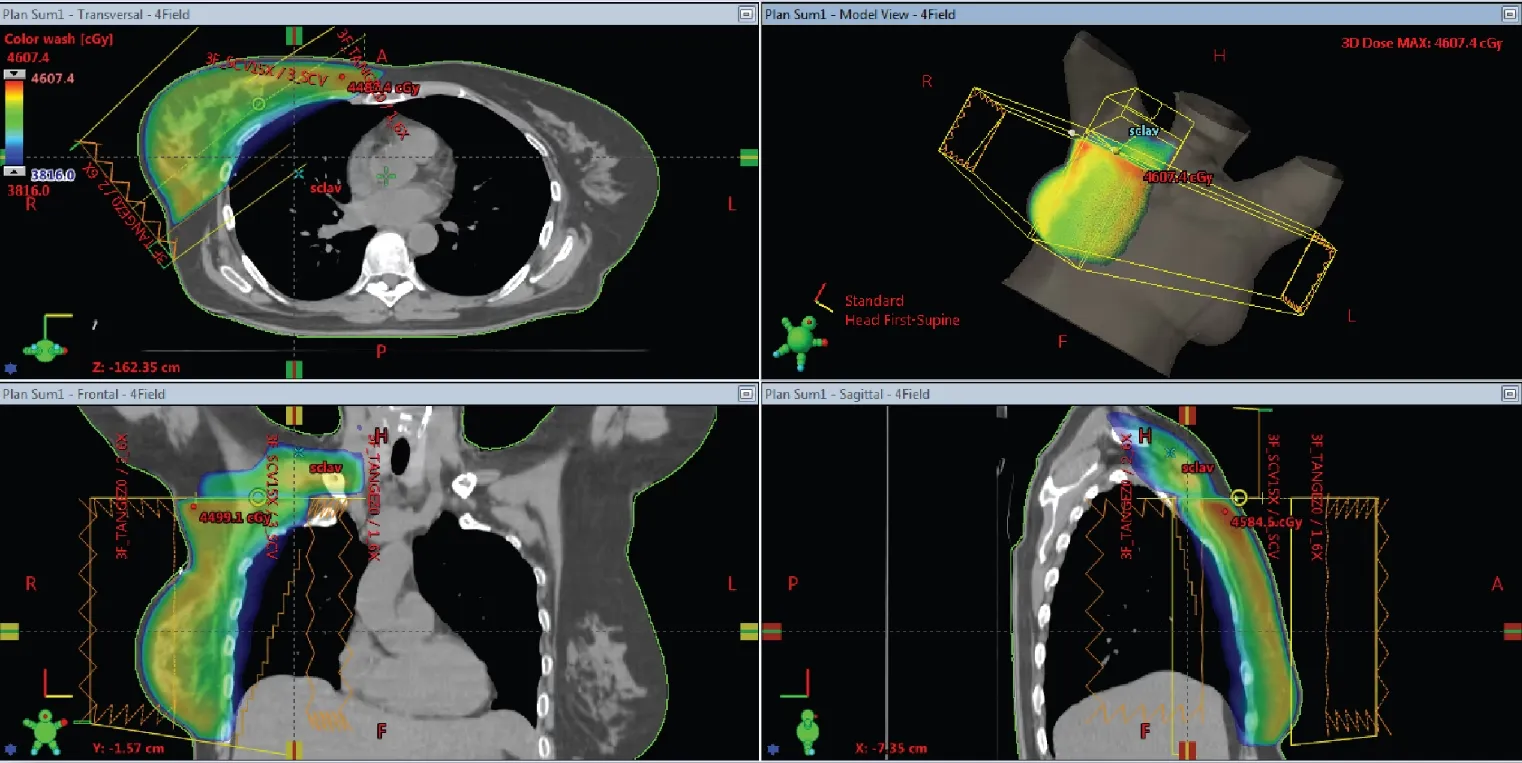

EZFluence is an FDA 510(k) cleared automated 3D planning software developed by Radformation. It simplifies and accelerates the creation of optimal fluence files and field-in-field plans for radiation therapy. Compatible with Eclipse™, Monaco®, and RayStation®, EZFluence integrates directly into the treatment planning system workspace, enabling clinicians to automate planning for any beam arrangement and treatment site—from head to toe. Designed to optimize electronic compensation (eComp) and field-in-field (FiF) techniques, EZFluence ensures consistency, efficiency, and confidence in every plan. It supports ASTRO guidelines for whole breast treatment and includes tools for simultaneous integrated boost, lung, pelvis, whole brain, and extremity planning.

- 3 & 4 Field Breast Planning:

- Automates SCLAV and PAB field weighting

- Controls match line in monoisocentric plans